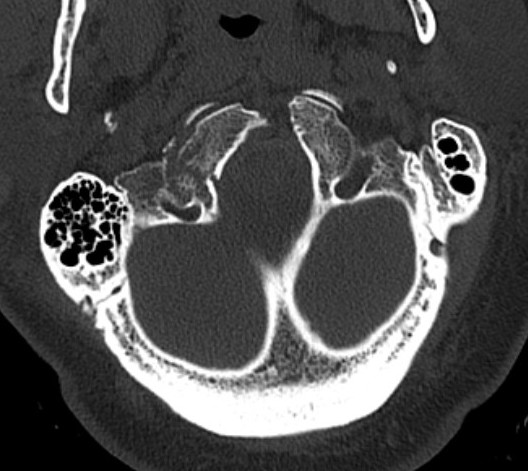

Type II: Occipital condyle fracture involving base of skull

Type III: Inferomedial alar ligament avulsion

Type II: Basal skull involvement